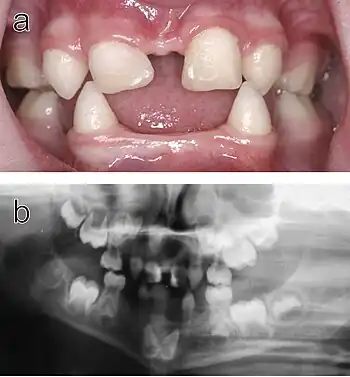

a) Intraoral view. Note that the upper incisors have been restored with composite material to disguise their original conical shape.

b) Orthopantomogram showing absence of ten primary and eleven permanent teeth in the jaws of the same individual.

Teeth